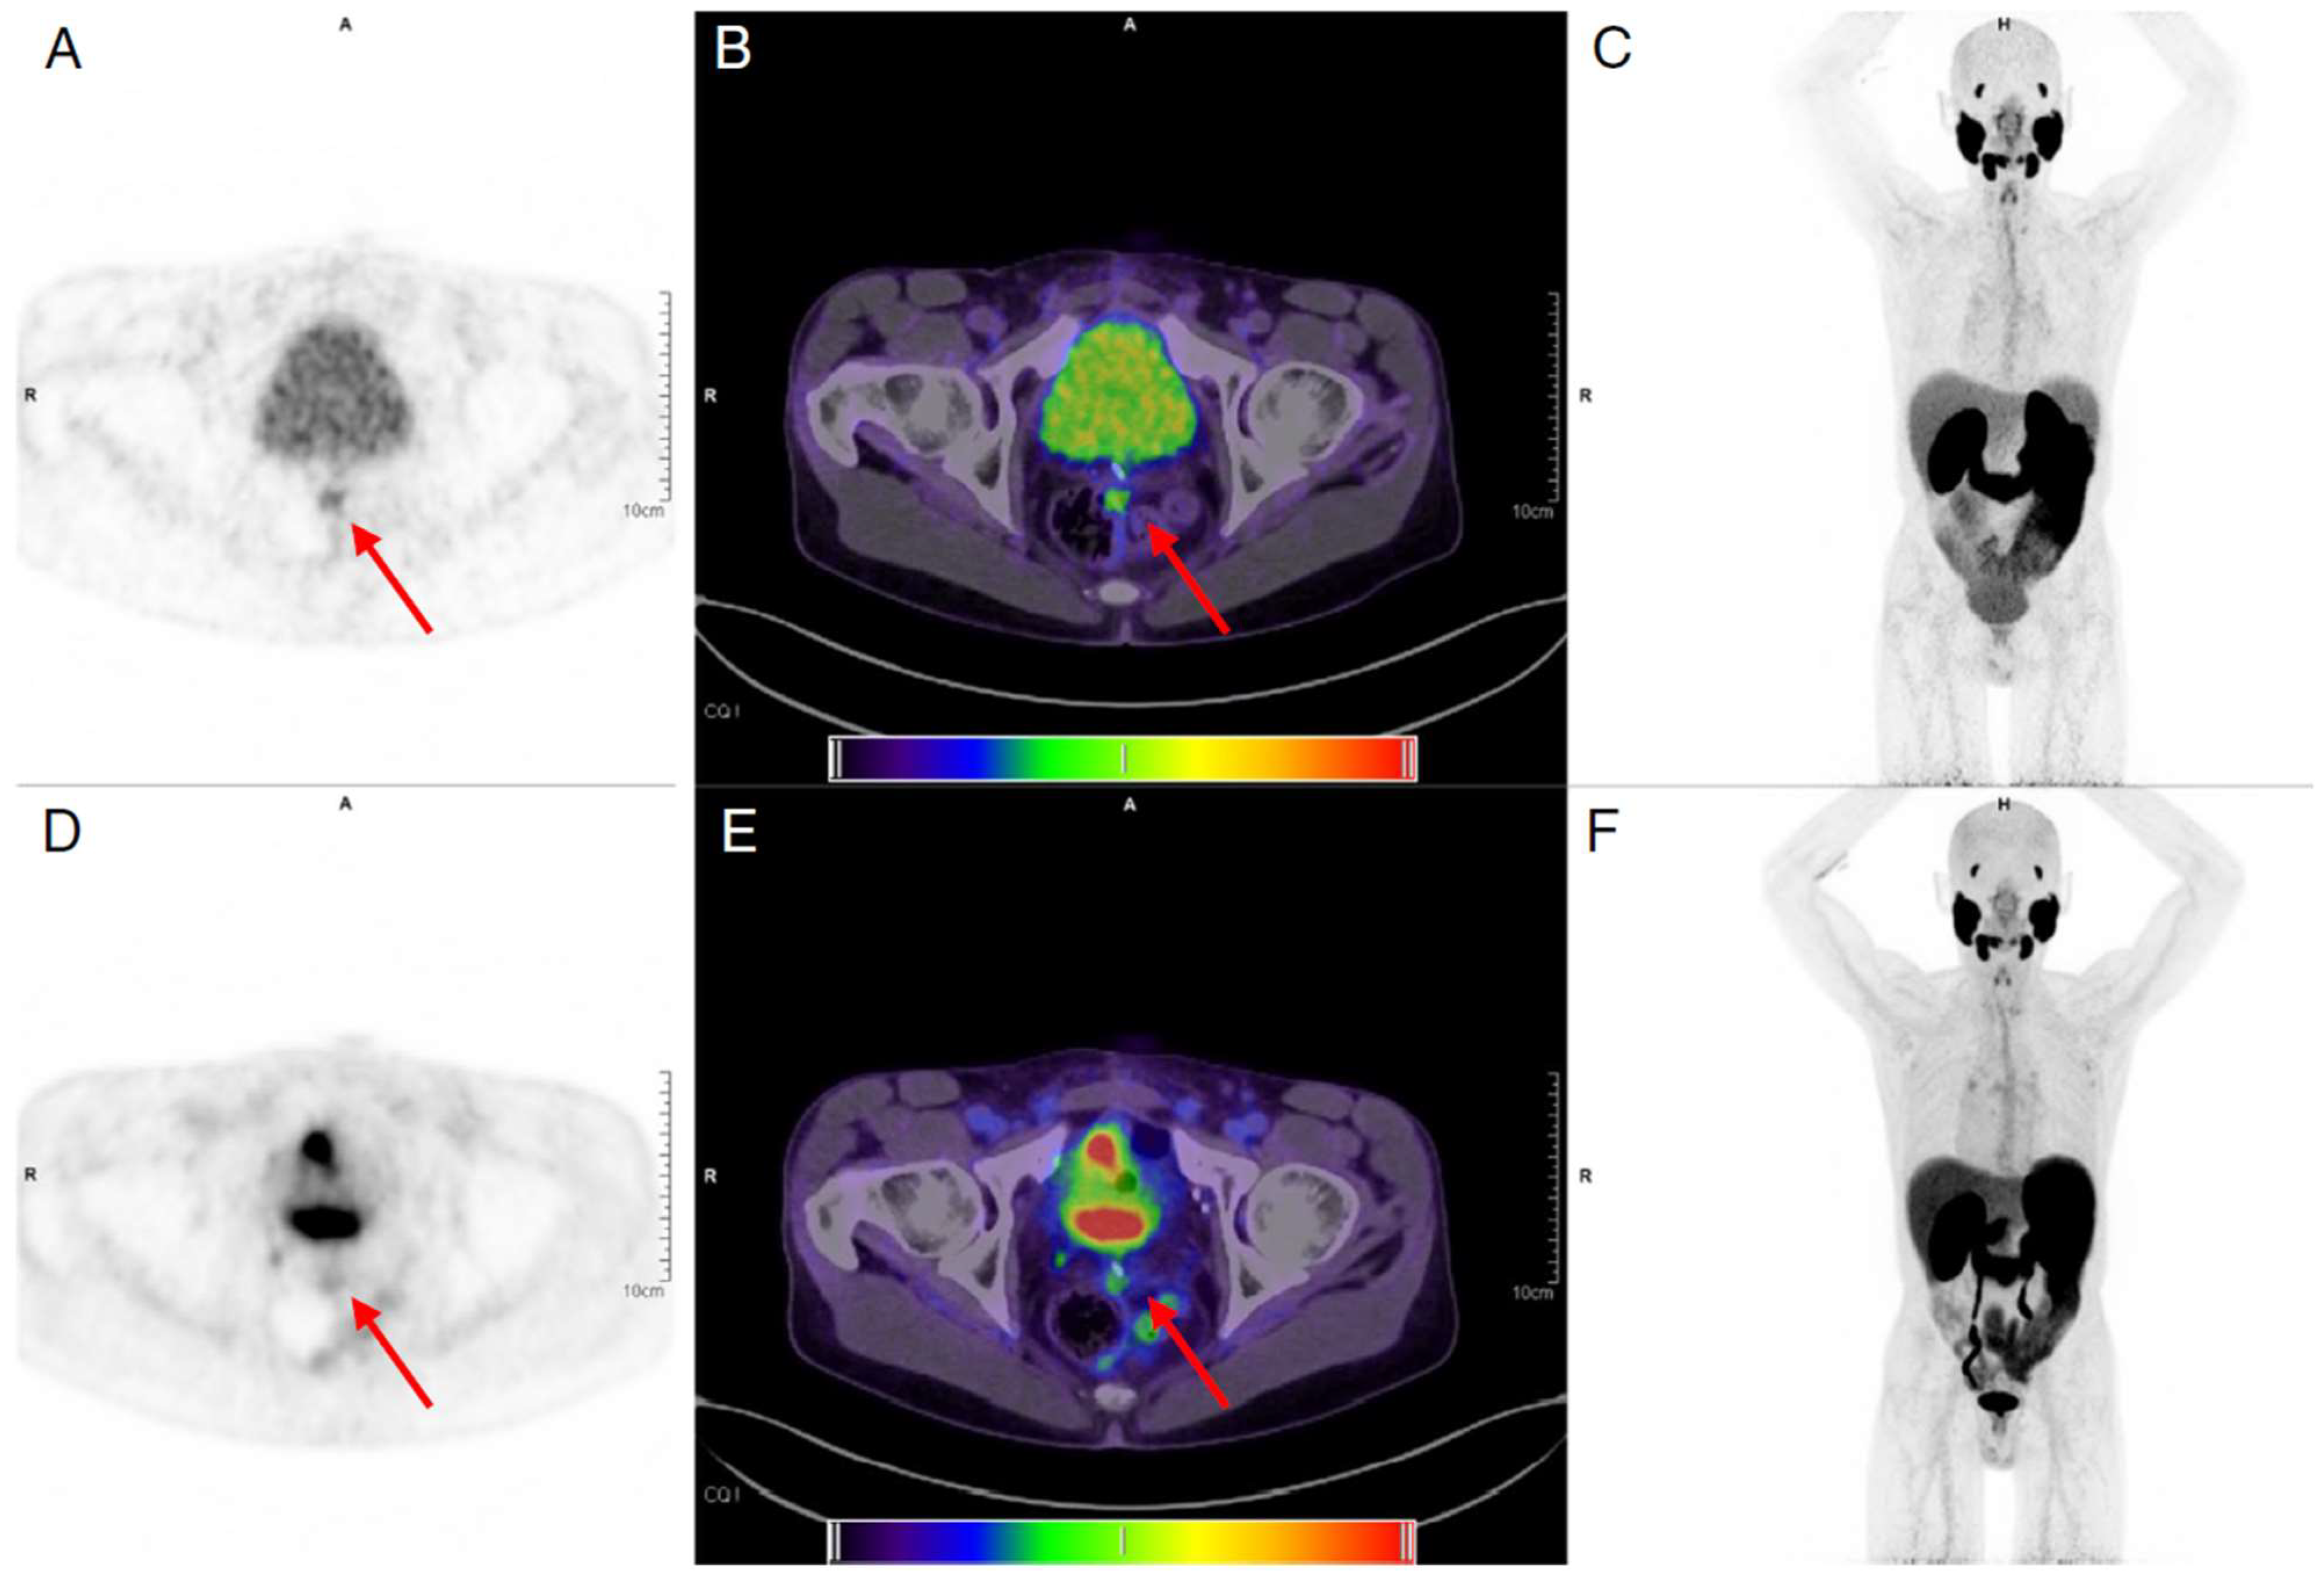

6. Dual Tracer

- Van Sluis, J.; Borra, R.; Tsoumpas, C.; van Snick, J.H.; Roya, M.; Ten Hove, D.; Brouwers, A.H.; Lammertsma, A.A.; Noordzij, W.; Dierckx, R.; et al. Extending the clinical capabilities of short- and long-lived positron-emitting radionuclides through high sensitivity PET/CT. Cancer Imaging 2022, 22, 69. [Google Scholar] [CrossRef]

- Liu, G.; Mao, W.; Yu, H.; Hu, Y.; Gu, J.; Shi, H. One-stop [(18)F]FDG and [(68)Ga]Ga-DOTA-FAPI-04 total-body PET/CT examination with dual-low activity: A feasibility study. Eur. J. Nucl. Med. Mol. Imaging 2023, 50, 2271–2281. [Google Scholar] [CrossRef]

- Alberts, I.; Schepers, R.; Zeimpekis, K.; Sari, H.; Rominger, A.; Afshar-Oromieh, A. Combined [68 Ga]Ga-PSMA-11 and low-dose 2-[18F]FDG PET/CT using a long-axial field of view scanner for patients referred for [177Lu]-PSMA-radioligand therapy. Eur. J. Nucl. Med. Mol. Imaging 2023, 50, 951–956. [Google Scholar] [CrossRef]